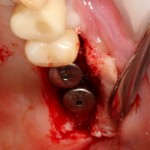

В описываемом клиническом случае нам нужно замещать достаточно большой объем костной ткани, поэтому использование ксенографта (Geistlich Bio-Oss) выглядит совершенно разумным. Мы смешиваем его с аутокостной стружкой, источником клеток и факторов роста костной ткани, в пропорции, примерно 50/50, получая, при этом, около 3 куб см готового к использованию графта:

С помощью него мы «достраиваем» недостающую часть альвеолярного гребня, полностью перекрывая импланты. Напомню, что субкрестальные Ankylos Dentsply Implants вполне допускают такой подход.

Костная ткань, в отличие от слизистой оболочки, регенерирует очень медленно. Если ее не отделить от быстрорастущих тканей, то место, где должна регенерировать костная ткань, быстро заполняется грануляциями — и, в итоге, для кости не остается пространства для роста. Чтобы отделить одно от другого, используются коллагеновые барьерные мембраны.

В нашем случае мы используем Geistlich Bio-Gide. Почему? Потому, что, имхо, это лучшее, что есть на рынке барьерных мембран. Почему? См. RegenerationDay.